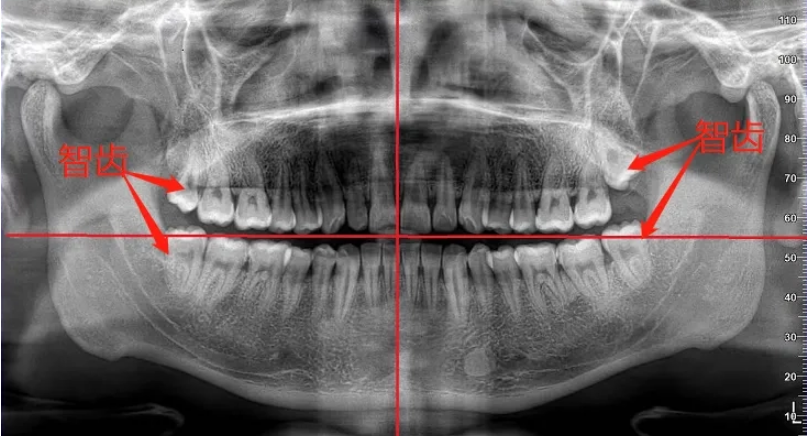

珠海維港口腔箍牙專家科普,除一般正畸學檢査專案外,還要著重進行以下檢査:1、X光檢査。X光全頜曲面斷層能全面地反應牙齒和齒槽骨的現狀。根尖片可顯示被移動牙的牙周...[詳細]